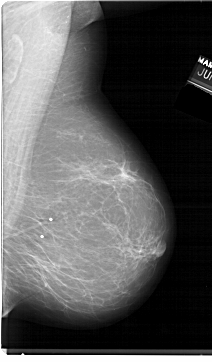

A_1398_1.RIGHT_MLO

RIGHT_MLO LINES 6871 PIXELS_PER_LINE 4021 BITS_PER_PIXEL 12 RESOLUTION 43.5 NON_OVERLAY